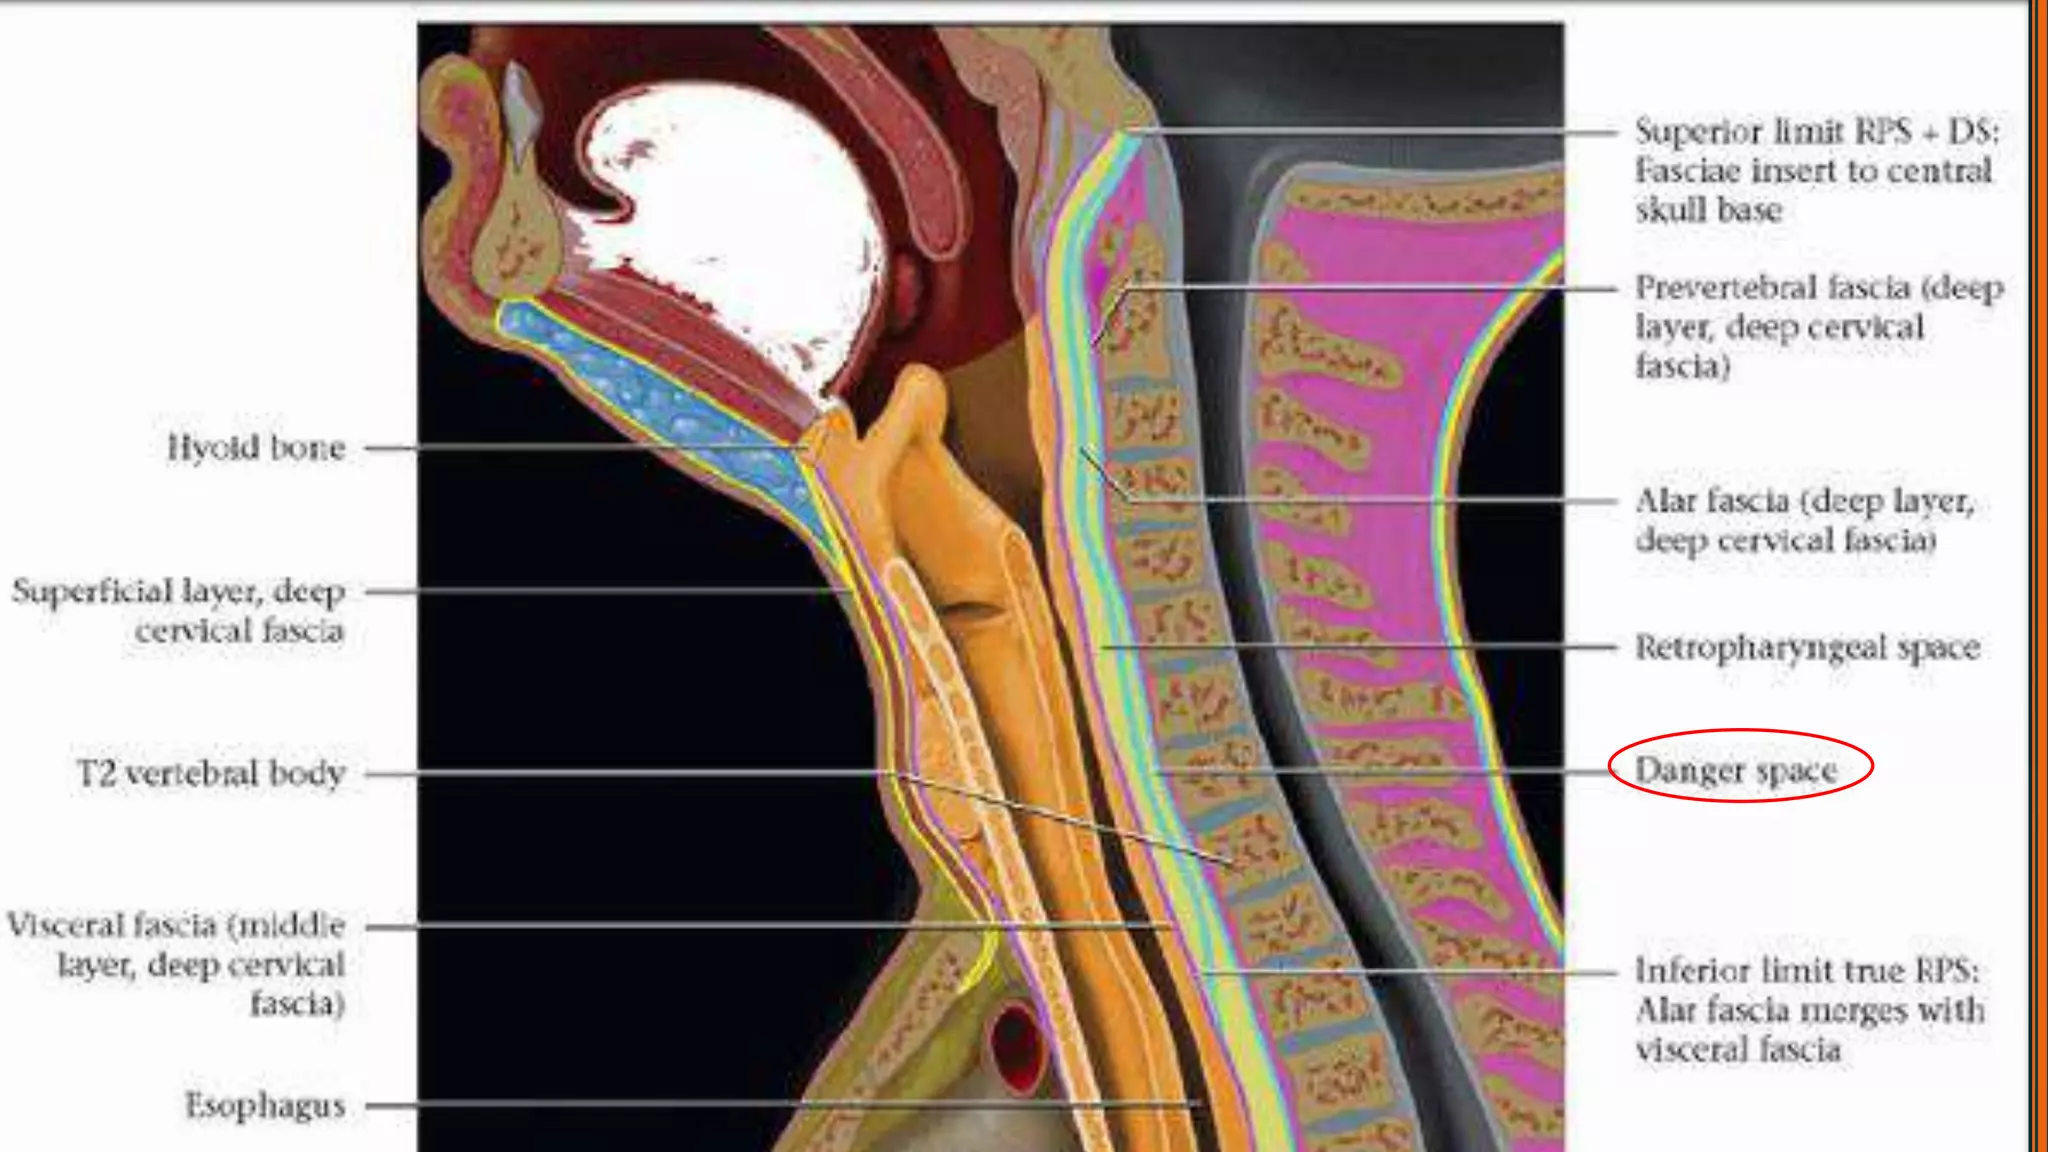

DANGER SPACE

 Posterior to the RPS.

 Bounded by the Alar fascia anteriorly and Prevertebral portion proper posteriorly.

 Extends from the skull base up to the diaphragm.

 Content : loose areolar tissue which provides easy pathway for the spread of infections.

 In healthy patients, it is indistinguishable from the retropharyngeal space. It is only

visible when distended by fluid or pus, below the level of T1-T6, since the

retropharyngeal space variably ends at this level.

Retropharyngeal Space

 The retropharyngeal space is posterior to the pharynx and oesophagus,

and extends from the base of the skull to a variable level between the T1

and T6 vertebral bodies 2.

 Between middle layer deep layer of deep cervical fascia.

 The main component of the retropharyngeal space is areolar fat.

DANGER SPACE  Posteriorto the RPS.  Bounded by the Alar fascia anteriorly and Prevertebral portion proper posteriorly.  Extends from the skull base up to the diaphragm.  Content : loose areolar tissue which provides easy pathway for the spread of infections.  In healthy patients, it is indistinguishable from the retropharyngeal space. It is only visible when distended by fluid or pus, below the level of T1-T6, since the retropharyngeal space variably ends at this level.